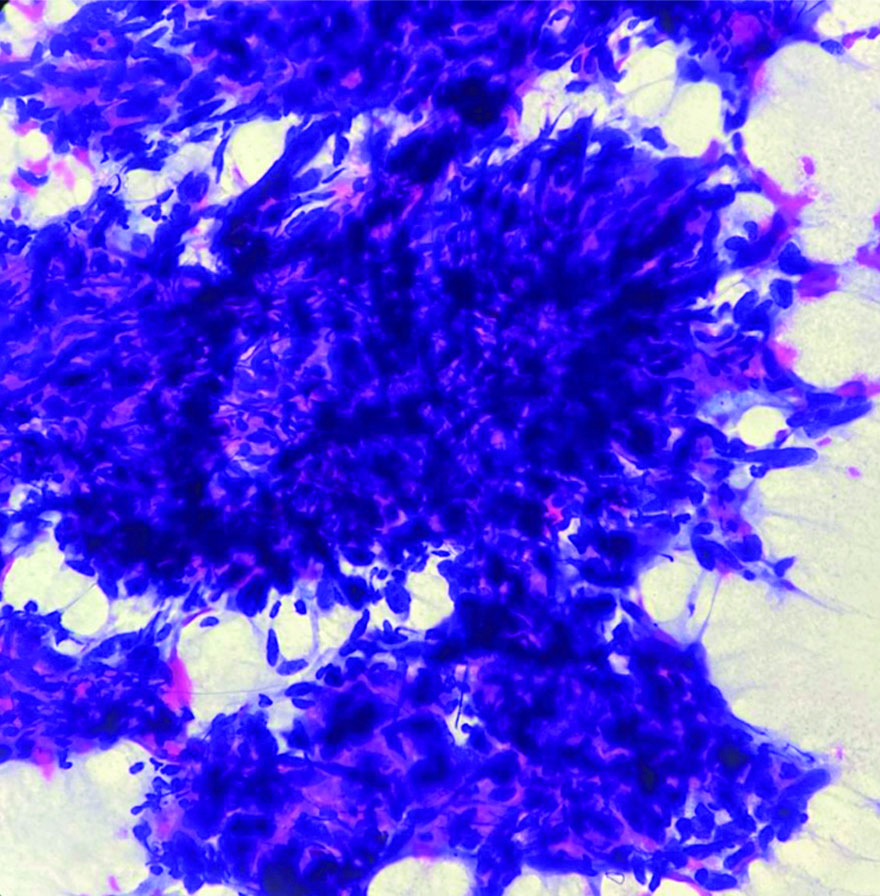

The patient underwent Ultrasonography (USG) of the left forearm, which showed a well-defined, heterogeneously hyperechoic lesion in the subcutaneous plane. There was no evidence of bony involvement and a radiodiagnosis of a soft-tissue tumour was given. Resonance Imaging (MRI) revealed a well-defined ovoid mass in the subcutaneous plane. The lesion was heterogeneously hyperintense with areas of central necrosis [Table/Fig-2]. The differential diagnosis included fibrosarcoma, dermatofibrosarcoma protuberans, poorly differentiated carcinoma, malignant fibrous histiocytoma nerve sheath tumour, along with the need for FNAC correlation. FNAC was carried out under USG guidance. The smears were of high cellularity, revealing multiple fragments of spindle nuclear cells [Table/Fig-3]. A few fragments showed peripheral nuclear palisading and attempted whorling. In some areas, the cell borders exhibited feathery margins [Table/Fig-4]. These elongated spindle nuclei showed moderate pleomorphism and were hyperchromatic. A few cells demonstrated bipolar blunting of nuclei and prominent nucleomegaly with uneven chromatin [Table/Fig-5]. The cytoplasm of these cells appeared to merge with intracellular hyalines. There were also a few spindle bare nuclei with atypia and infrequent mitosis in the background. The diagnosis of malignant spindle cell neoplasm of peripheral nerve sheath tumour (MPNST) was offered.

FNA smear shows fragments and clusters of pleomorphic spindle nuclear cells (Papanicolaou stain, 10x).

FNA smear shows indistinct and feathery cytoplasmic borders (Papanicolaou stain, 40x).

FNA smear shows polygonal-shaped highly pleomorphic nuclei with standout nucleomegaly (Papanicolaou stain, 40x).

There are few studies in the literature where cytodiagnosis of MPNST has been made [3-6,10-12]. The observations made by the aforementioned authors detailed the findings as follows: i) highly cellular smears; ii) large sheets and groups of elongated, plump spindle cells; iii) cell clusters that also showed nuclear palisading in some cases; iv) ill-defined and merging cytoplasmic borders; v) wavy and slender nuclei with moderate to severe pleomorphism, containing uniform chromatin with prominent nucleoli; vi) mitotic figures observed in a few cases; and vii) a myxoid background consisting of fine, fibrillary stroma.

Wakely PE et al., detailed cytomorphological features in 55 cases diagnosed with MPNST [13]. They described cellular smears containing syncytial clusters and singly dissociated populations of uneven-sized cells. These cells were elongated, with some oval cells having smooth borders but inconsistently tapered. The cells contained granular, dispersed chromatin and there was a fibrillary metachromatic stroma in the background.

The cytomorphological features observed in the present case for diagnosing the malignant spindle cell type of PNST were similar to those in the studies mentioned above.